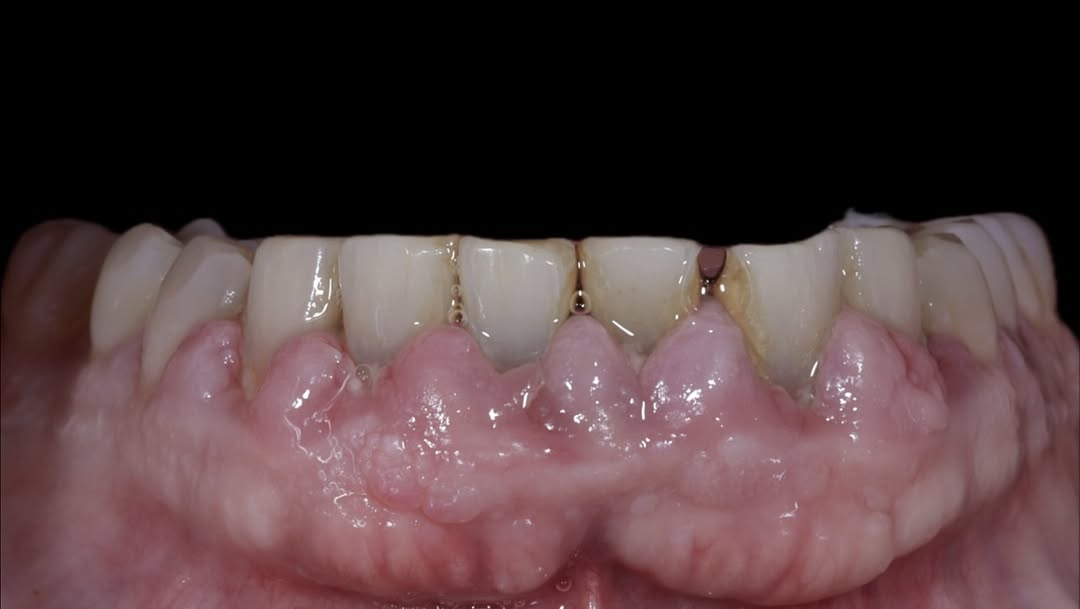

Se presenta un caso clínico de restauración directa en resina composite, ejemplo del valor de la precisión y la técnica meticulosa incluso en procedimientos considerados rutinarios dentro de la práctica diaria. El caso pone en evidencia la importancia del control de la morfología, la textura y la integración cromática, así como del adecuado aislamiento del campo operatorio y la estratificación del material, factores determinantes para conseguir un resultado natural, funcional y duradero. A través de una ejecución cuidadosa, se logró una restauración estéticamente imperceptible y funcionalmente estable, que respeta los principios de mínima invasión y adhesión efectiva. Este tipo de procedimientos, aunque cotidianos, reflejan la constancia y el nivel de exigencia clínica necesarios para ofrecer odontología de calidad en todos los casos, independientemente de su complejidad.

Ya se han realizado la extracción de los dientes 12, 11, 21, 22 para garantizar el cierre de tejidos blandos. El día de la cirugía, el alumno verá todo el procedimiento en una pantalla en directo en la sala de cirugía, ya que todo será realizado con un microscopio operatorio.

Se extraerán los